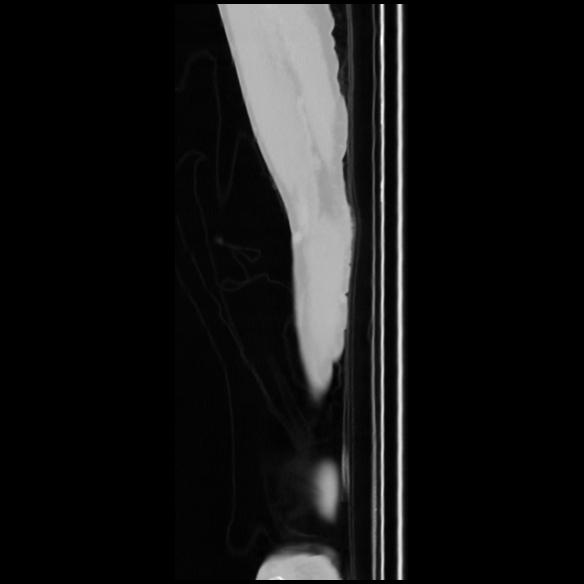

7 CUERPO,CE,Sagittal,3.000,CUERPO,Sagittal,